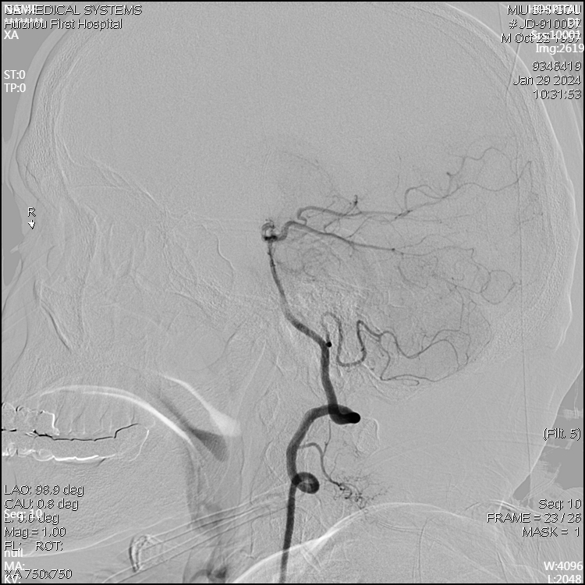

急诊DSA未见畸形血管。

急诊DSA(右侧颈内正位)